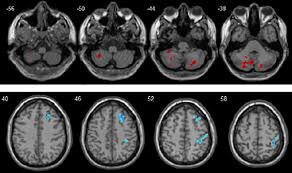

تصویربرداری تشدید مغناطیسی MRI یکی از مهم‌ترین ابزارهای پزشکی برای بررسی مغز و تشخیص بیماری‌های پیچیده است. اما تا همین چند وقت پیش، تحلیل این تصاویر زمان‌بر، پرهزینه و نیازمند تخصص فراوان بود. اکنون با پیشرفت هوش مصنوعی، سیستم‌هایی توسعه یافته‌اند که می‌توانند در عرض چند ثانیه MRI مغز را بخوانند، تشخیص دهند و نتایج را به پزشک ارائه دهند؛ تغییری بزرگ در مسیر تشخیص پزشکی. این پیشرفت می‌تواند زندگی میلیون‌ها نفر را در سراسر جهان متحول کند؛ به‌ویژه در شرایط اورژانسی که هر ثانیه اهمیت دارد.

نمونه‌های MRI واقعی را دیده یاد گرفته الگوهای غیرطبیعی را تشخیص دهد و می‌تواند نشانه‌هایی مثل: سکته، تومور، خونریزی مغزی، التهاب و آسیب‌های بافتی را در تصاویر MRI شناسایی کند. این تحلیل نه‌فقط سریع‌تر، بلکه در بسیاری موارد دقیق‌تر از چشم انسان عمل می‌کند.